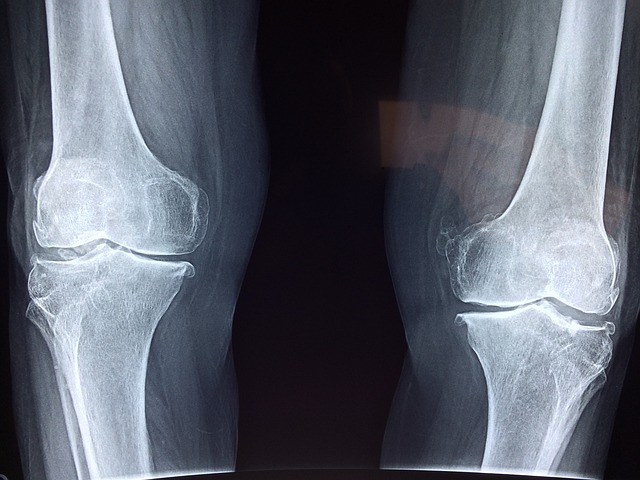

관절 건강은 일상생활의 편안한 활동을 위해 필수적인 요소입니다. 통증이 있는 관절 부위를 최대한 사용하지 않는 것은 관절염을 예방하고 건강한 관절을 유지하는 데 중요합니다. 뿐만 아니라, 꾸준한 관절영양제의 섭취도 관절 건강에 도움이 될 수 있습니다. 이번 포스트에서는 약사들이 추천하는 관절에 좋은 영양성분에 대해 알아보고, 이를 통해 올바른 영양제를 선택하는 데 도움이 되도록 하겠습니다.

관절영양제의 주요 성분을 크게 정리해보면, 연골 구성성분인 글루코사민과 콘드로이친이 관절과 연골에 직접적인 지원을 제공합니다. 더불어 2형콜라겐과 히알루론산을 추가하면 시너지 효과를 발휘하여 더욱 효과적입니다. 또한, 염증을 완화하고 관절에 유익한 성분으로는 식이유황 MSM, 초록입홍합 커큐민, 보스웰리아 등이 포함됩니다. 조직과 뼈에 필요한 칼슘, 마그네슘, 비타민D, 망간, 구리, 비타민 C 등도 중요한 성분입니다. 이러한 성분들을 종합적으로 고려하여 영양제를 선택하면 관절건강에 도움이 될 것입니다. 관절에 좋은 영양성분 BEST 7을 알아보고 각 성분의 효능에 대해 자세히 알아보도록 하겠습니다.